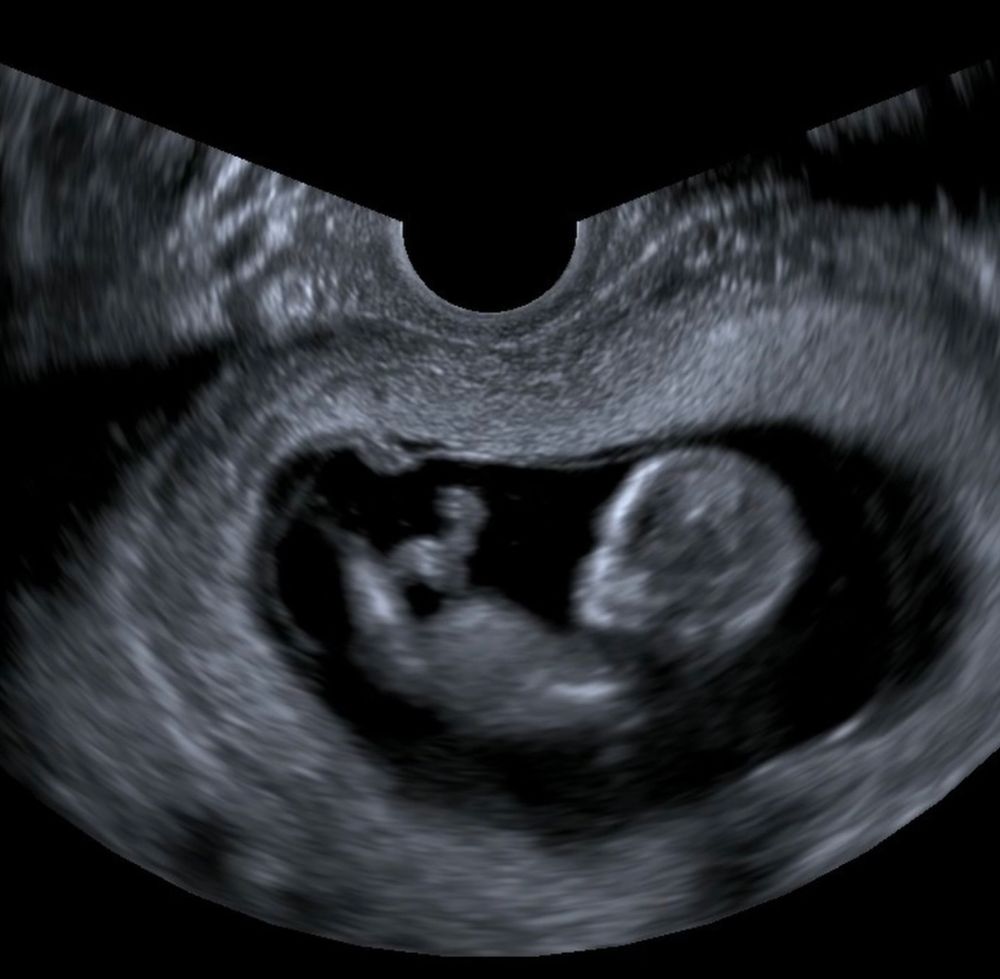

Мальчик или девочка?

Мальчик 👍

Мальчишка 100% вон как торчит)